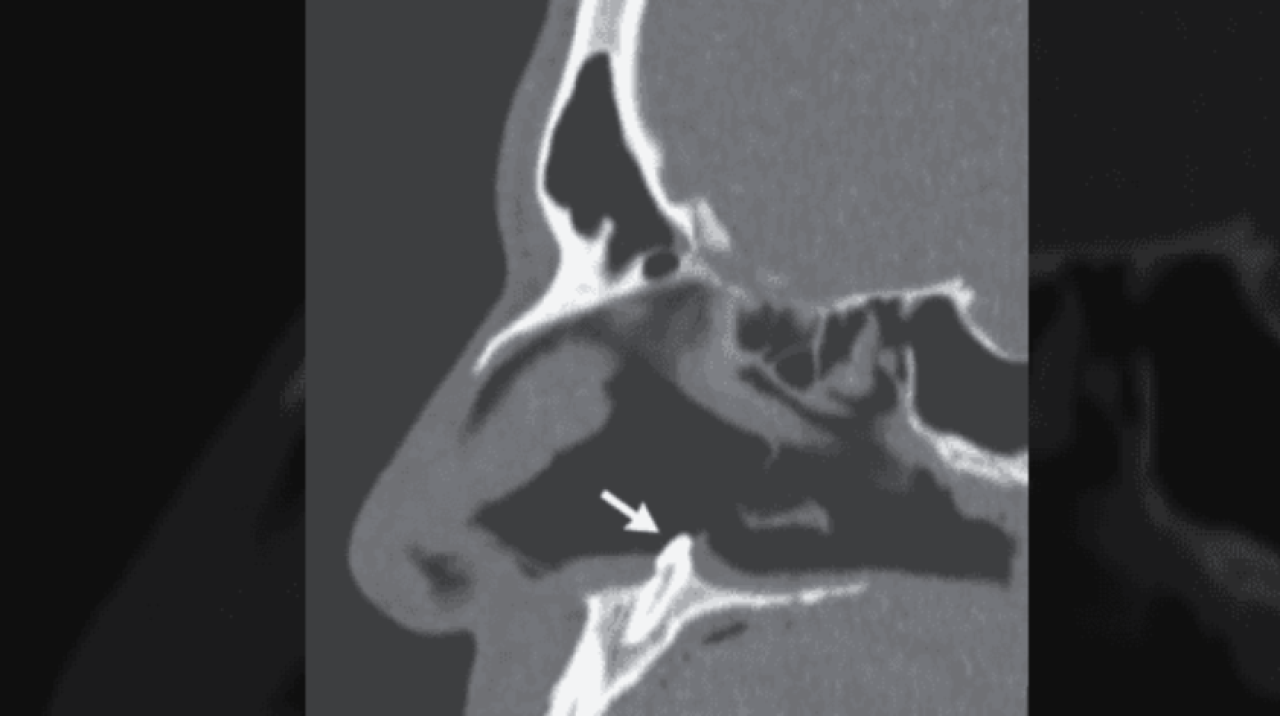

Amerika Birleşik Devletleri'nin New York eyaletinde meydana gelen olay, tıp literatürüne girdi. Uzun süredir burun tıkanıklığı şikayeti yaşayan adam, durumu dayanılmaz hal alınca doktora gitti. Doktorlar, yaptıkları ilk muayenenin ardından adamın burnunda daha önce karşılaşmadıkları bir manzara gördü. Çünkü adamın burnundaki tıkanıklığa neden olan şey, orada olmaması gereken dişti.

Doktorlar, karşılaştıkları bu ilginç durumun ardından ne yapacaklarına karar vermek için acil olarak toplantı kararı aldı. Yapılan görüşmeler ve tetkikler sonucunda adamın hemen ameliyata alınması kararlaştırıldı. New York'taki Mount Sinai Hastanesi'nde gerçekleştirilen ameliyatın ardından 38 yaşındaki adamın burnundaki diş, başarılı şekilde çıkarıldı.

Tıp dünyasında daha önce eşine çok az rastlandığı belirtilen olay, New England Tıp Dergisi'nde de yayınlandı. Dergideki yazıda, "Hasta bir kaç yıldan bu yana burun tıkanıklığı yaşadığını belirtti ancak daha önce yüz travması ya da başka bir anormallikle karşılaşmadığını anlattı. İlk muayenenin ardından buruna takılan kamera sayesinde, burunda olmaması gereken bir diş parçası tespit edildi. Bu parça başarılı ameliyat sonucu alındı" ifadelerine yer verildi.